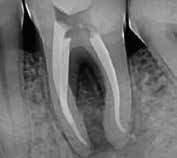

Fase diagnostica, che prevede una prima anamnesi clinica, una radiografia pre-operatoria per interpretare l’anatomia endodontica, al fine di definire un corretto piano di trattamento.

La diagnosi in endodonzia non può prescindere dall’esecuzione di esami radiologici accurati, in grado di mostrare l’esatta anatomia delle strutture dentali, in particolare dell’anatomia radicolare e dei tessuti di supporto.

Le apparecchiature radiologiche convenzionali (endorali) forniscono una rappresentazione bidimensionale di strutture anatomiche tridimensionali.

Questa immagine “appiattita” può nascondere, sovrapponendole, alcune aree anatomiche, soprattutto quelle in senso bucco-vestibolare (spessore dei tessuti).

Anche adottando tecniche radiografiche in grado di migliorare la qualità dell’immagine (tecnica del cono lungo con centratore “tipo Rinn”, proiezione dei raggi con inclinazione mesio-distale), i limiti tecnologici imposti dagli apparecchi endorali non sempre sono superabili.